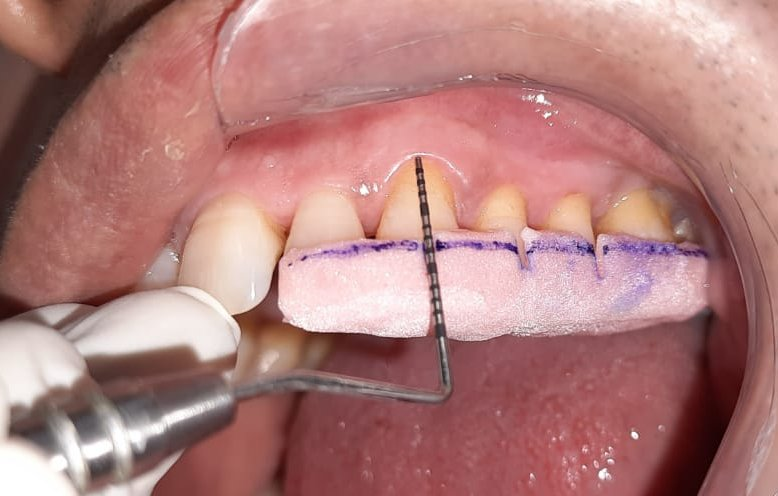

Gum Drop Technique With Titanium Prepared Platelet Rich Fibrin For The Treatment Of Multiple Gingival Recession : A Clinical Study

Investigators: Dr. Archita Datta, Dr. Arundeep Kaur Lamba, Dr.Shruti Tandon

Dental patients of all ages are increasingly concerned about their smile and overall appearance and are particularly unhappy when they have esthetic issues and dental pain associated with exposed roots. Gingival recession is the oral exposure of the root surface due to a displacement of the gingival margin apical to the cemento-enamel junction. Recession seen in healthy patients is mainly due to oral care that is “too much of a good thing” whereas recession seen in periodontally diseased patients is likely due to a chronic inflammatory process that may represent years of “doing too little of a good thing”. Regardless of the frequency & intensity of the oral hygiene, the symptom that brings periodontally healthy and unhealthy patients with recession to the dental clinic is a very unpleasant side effect common to both groups – dentin hypersensitivity.

This study is a prospective pre & post interventional study that involves 40 patients complaining of dentinal hypersensitivity along with at least 2 recession‐type defects affecting adjacent teeth in esthetic areas of the mouth. This technique is minimally invasive and it addresses the goals of root recession coverage with a biological approach to stimulate healing, reduce inflammation during healing, and provide long term stability of the repositioned gingival margin. A less invasive surgical approach has shown higher patient acceptance. Results observed on Patient centered outcomes i.e dentinal hypersensitivity &esthetic score have shown significant difference. The new biological approach of using T-PRF has provided a stimulus to growth factors encouraging new attachment of the gingival tissue to the root surface. This has led to identifying a new economical and readily available alternative to commercially available allografts. The technique has shown success and will work as a foundation step for future research on titanium prepared platelet rich fibrin (T-PRF) as an autologous graft for various therapeutic procedures.